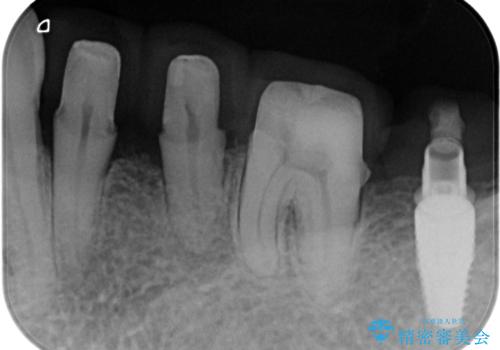

歯周病再生治療と歯周ポケット除去 歯周外科手術

重度の歯周病で再生療法の適応ではない最後方臼歯は抜去行い、インプラント治療、

がたつきの強い天然歯を矯正治療で整えたのち、再生治療、歯周ポケットを除去する歯周外科手術を行いました。

歯周病の問題が解決したのち、歯の揺れを抑えるべくセラミッククラウンで連結補綴をおこなっています。

再生療法を行ったことで、抜歯をされてもおかしくなかった歯を、残すことができました。